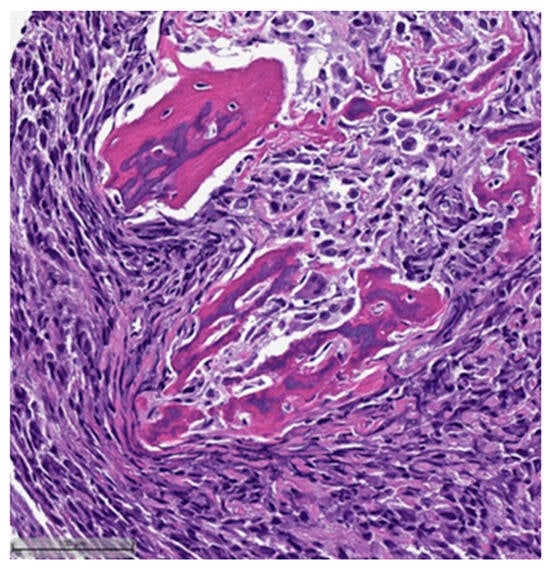

This system is primarily based on the specific metaplastic elements present within the tumors, while also highlighting the potential overlap that can exist between various histological subtypes [6]. Consequently, numerous cases diagnosed as MpBCs, are accompanied by a detailed description of the histological component or a combination of different component types and/or differentiations. The following figures illustrates a few examples: spindle cell carcinoma component with pleomorphic features (Figure 4), metaplastic breast carcinoma with chondroid differentiation (Figure 5), metaplastic breast carcinoma with a matrix-producing component (Figure 6), metaplastic breast carcinoma with osseous differentiation (Figure 7), and extensive trabeculae bone and hematopoietic tissue (Figure 8).

Figure 7.

Metaplastic breast carcinoma with osseous differentiation (H&E, 20×).

Figure 8.

Same case in Figure 7: showing extensive obvious bone trabeculae and hematopoietic tissue (H&E, 20×).